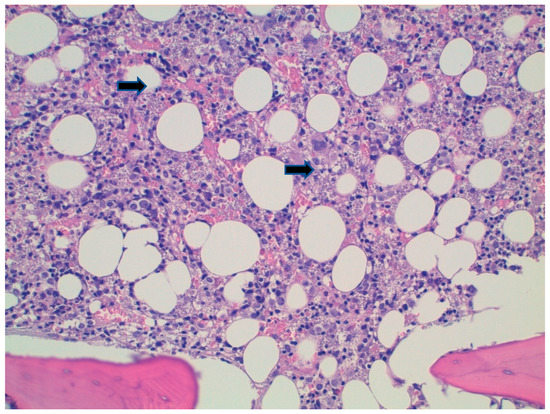

2. Case Report